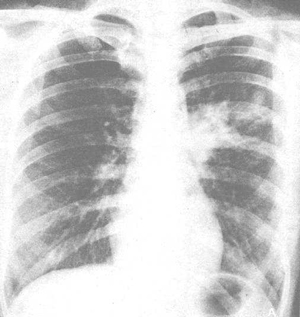

支原体肺炎的影像学表现

1.早期双肺纹理增多模糊与网状阴影,以间质病变为主,与病毒性肺炎、机遇性肺炎等无法区别。

2.中下肺野较低密度斑片状的阴影.密度不均,常呈单侧。

3.一个肺叶或肺段实变,但边缘模糊呈网状结节状,无清晰的分界,常伴有肺门淋巴结肿大,并随症状的吸收而缩小或消失。

4.并发症较多,尤其胸膜炎的发生率高,主要表现为胸腔积液和胸膜反应性增厚。

5.一般两周左右开始吸收,1-2月可明显吸收或完全吸收。

(如图所示,正位显示左中肺叶模糊阴影,左肺门增大。)